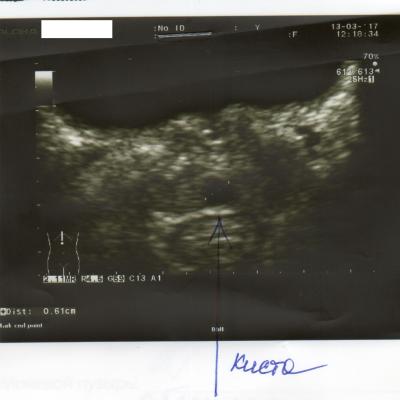

Здравствуйте. Мне 29 лет. Вес 60 кг. Рост 174см. Пол мужской. Беспокоят частые позывы к мочеиспусканию уже где-то пол года. От 6-8 раз в сутки. Раньше столько не ходил. Чувствую что мочевой пузырь не совсем полный. Где то 100-150мл и бегаю в туалет. Очень давно при прыжках с небольшой высоты была резкая боль в промежности. Сейчас очень редко бывает, не знаю простата это болит или что-то другое. Ночью встаю 1 раз. Струя нормальная. Делал УЗИ несколько раз. Врач пальцем проверил простату, сказал, что с левой стороны прощупываются неровности. Боли при ощупывании не было, было чувство на головке, как будто позыв к мочеиспусканию сильный. Сразу ершиком взял анализ ПЦР на инфекции. Нашли только гарднерелла. Сразу начал выписывать антибиотик. Я сказал, не лучше будет на чувствительность сделать анализ. Сказал, зачем терять время. У меня во вложении назначение, ответы анализа, УЗИ.

5. Из клиники только частые позывы. Есть какие то изменения в простате по УЗИ, но я до сих пор сомневаюсь есть ли у меня хр. простатит и какой именно(синдром тазовой боли, инфекционный и др.). Что еще нужно сделать, чтобы определиться с причиной частых позывов?